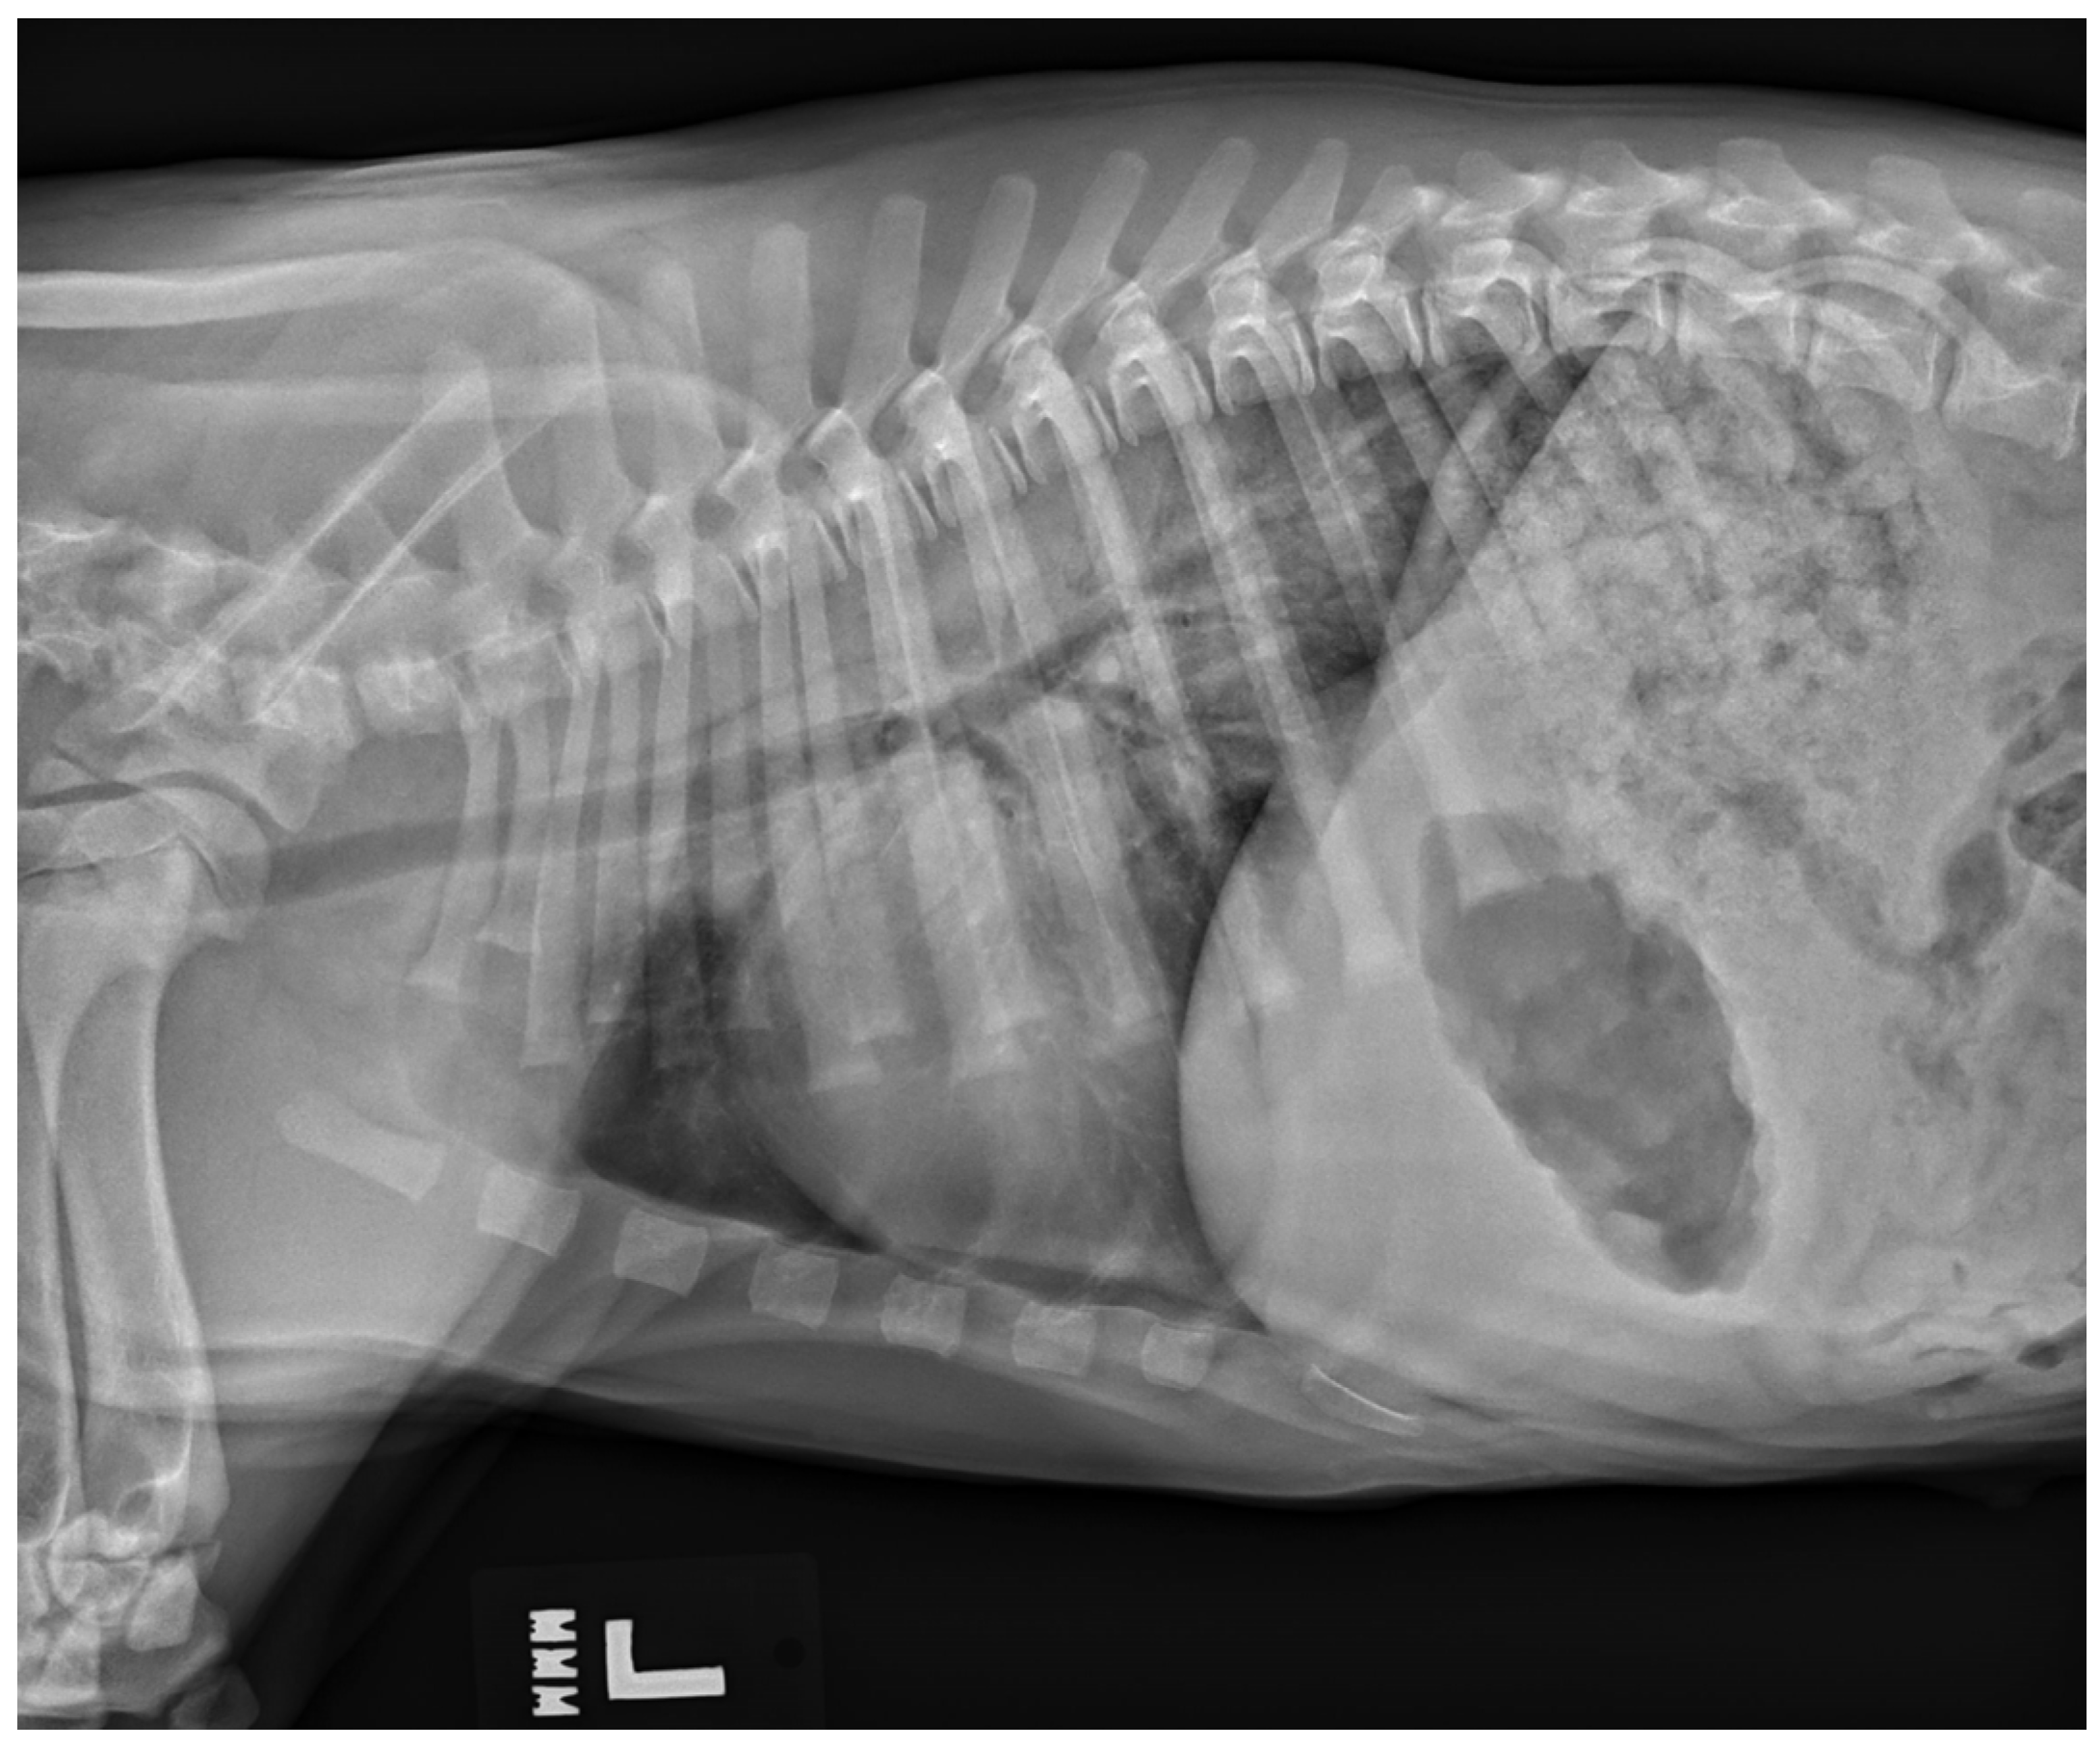

6.6. Neurogenic Pulmonary Edema

While uncommon, a type of non-cardiogenic pulmonary edema termed neurogenic pulmonary edema (NPE) can arise after severe or ongoing seizure activity. The increase in intracranial pressure during a seizure leads to a surge in catecholamines, resulting in vasoconstriction and increased vascular permeability [32]. The resulting alveolar capillary fluid leakage causes pulmonary edema [6,32]. Diagnosis of neurogenic pulmonary edema is made from thoracic radiographs. A bilaterally symmetric interstitial-to-alveolar pattern most prominent in the caudodorsal lung fields is commonly seen but may take upwards of 24 h to form (see Figure 3). Thoracic radiographs may also be useful to serve as a baseline for patients at high risk of developing non-cardiogenic pulmonary edema secondary to seizures, and they may also be used to rule out evidence of aspiration pneumonia/pneumonitis and evidence of primary or malignant neoplasia of the thoracic cavity. Unlike with cardiogenic pulmonary edema (CPE), the use of diuretics such as furosemide is controversial [33] and may not be recommended as a first-line treatment with NPE as volume overload is not present in NPE as it is with CPE. While there have been speculations that furosemide causes vasodilation leading to improved ventilation/perfusion mismatch, studies showing its consistent use for NPE are lacking [32]. There is also skepticism of furosemide’s benefit as it likely leaves behind leaked proteins and does not necessarily prevent further vascular leakage of fluid. Treatment relies on supplemental oxygen as needed, and in severe cases, mechanical ventilation may be required [32].

Figure 3.

A left lateral thoracic radiograph showing the classic caudodorsal interstitial-to-alveolar pulmonary pattern of a patient with neurogenic pulmonary edema.